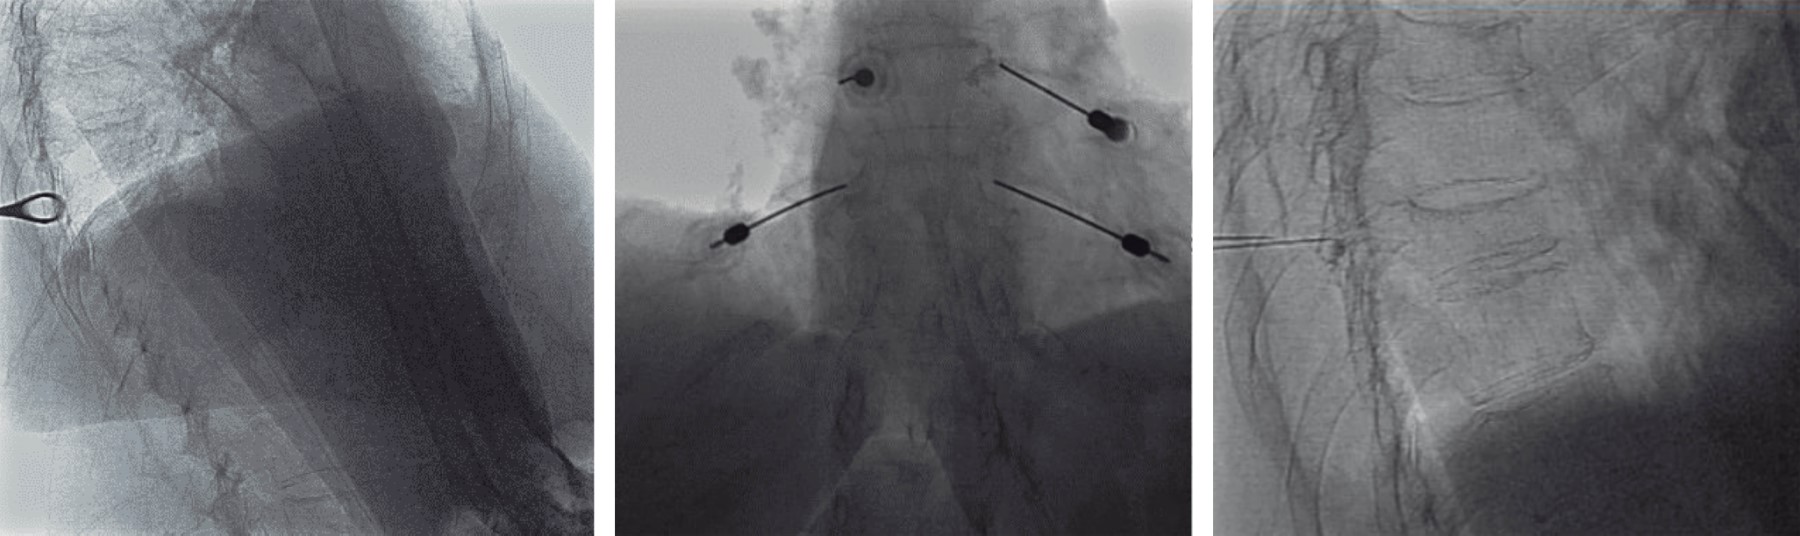

Procedimiento: confirmadas múltiples fracturas vertebrales toracolumbares mediante resonancia magnética (Figura 1A y B), se realizó un bloqueo de ramas medias en posición sedente bajo guía fluoroscópica utilizando el equipo de rayos X Allura Xper FD20 (Philips Medical Systems, Países Bajos) (Figura 1C y D).

Preparación de la mezcla de medicamentos: Para cada rama media se utilizaron 10 ml de una mezcla compuesta por 1 ml de metilprednisolona (40 mg/ml), 9 ml de ropivacaína (2 mg/ml) y 1 ml de medio de contraste no iónico a base de iopromida (370 mg de yodo/ml). Esta combinación permitió la visualización adecuada bajo fluoroscopia y proporcionó tanto analgesia como efectos antiinflamatorios en el sitio del bloqueo (Figura 2).